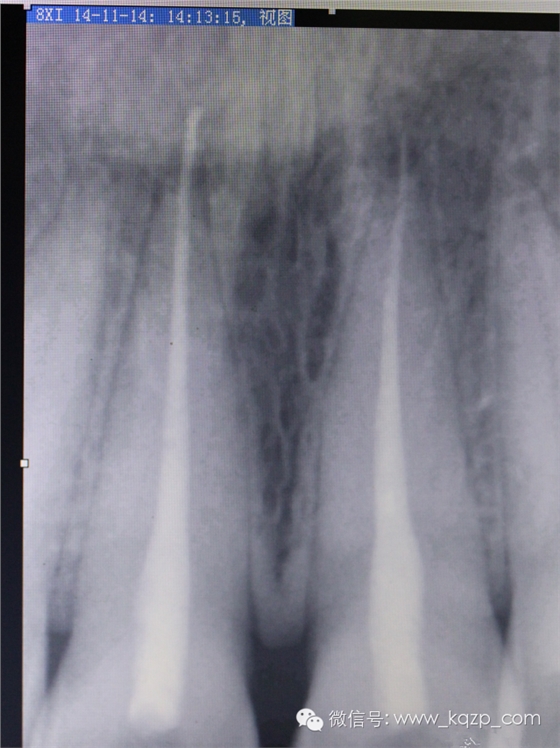

拍片見35根管治療后超充。

拍片,

順手把工作長(zhǎng)度也確定下。